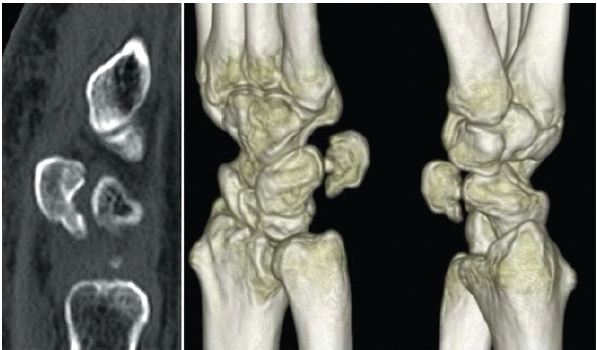

A 64-year-old right-handed woman presented with the sudden onset of severe right wrist pain sustained after a fall. Physical examination demonstrated swelling and tenderness along the ulnar aspect of the volar wrist. Plain radiographs and computed tomography (CT) scans revealed a comminuted intra-articular pisiform fracture featuring a small proximal fragment and articular incongruity with a cortical gap and a step-off (Fig. 1 and 2).

Figure 2: Computed tomography displays a small proximal fragment (3.7 mm) comminution, and pisotriquetral joint incongruity characterized by a cortical gap and a set-off.

Sagittal CT reconstruction confirmed that the fragment measured 3.7 mm in size (DICOM viewer, Horos Project). Pre-operative planning indicated that stable fixation with screws or wires was technically unfeasible due to the small fragment size and poor bone stock. Given the displacement, articular incongruity, and instability, non-operative management was considered unlikely to restore anatomical alignment or bone union. Pisiform excision was considered but deferred as no degenerative changes in the pisotriquetral joint were evident, and joint preservation was preferred. Moreover, ORIF with hook plate fixation was selected, and surgery was performed 8 days post-injury.